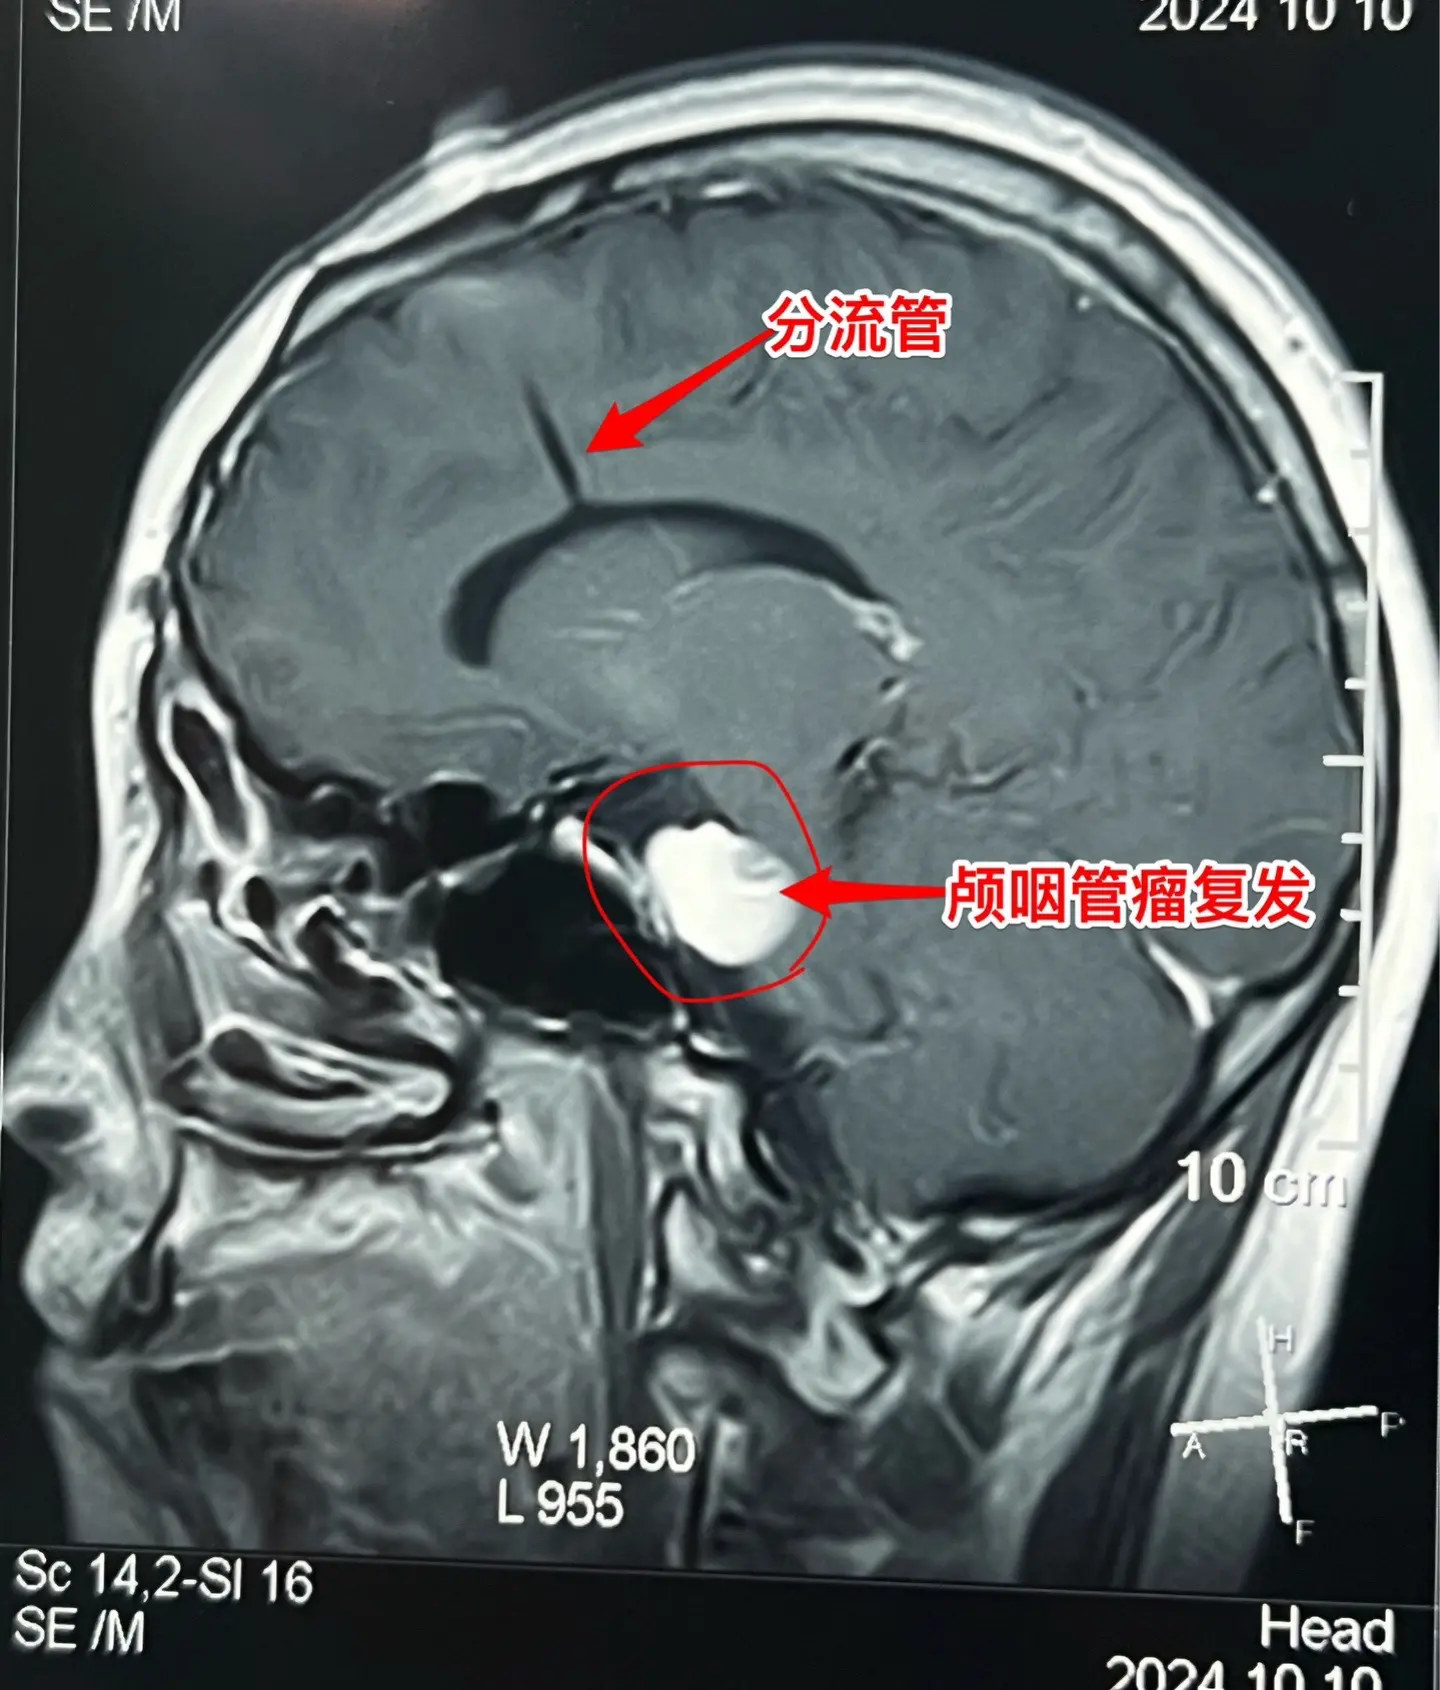

3次复发的颅咽管瘤也要积极治疗。16岁杭州女生,因颅咽管瘤于10年前在...